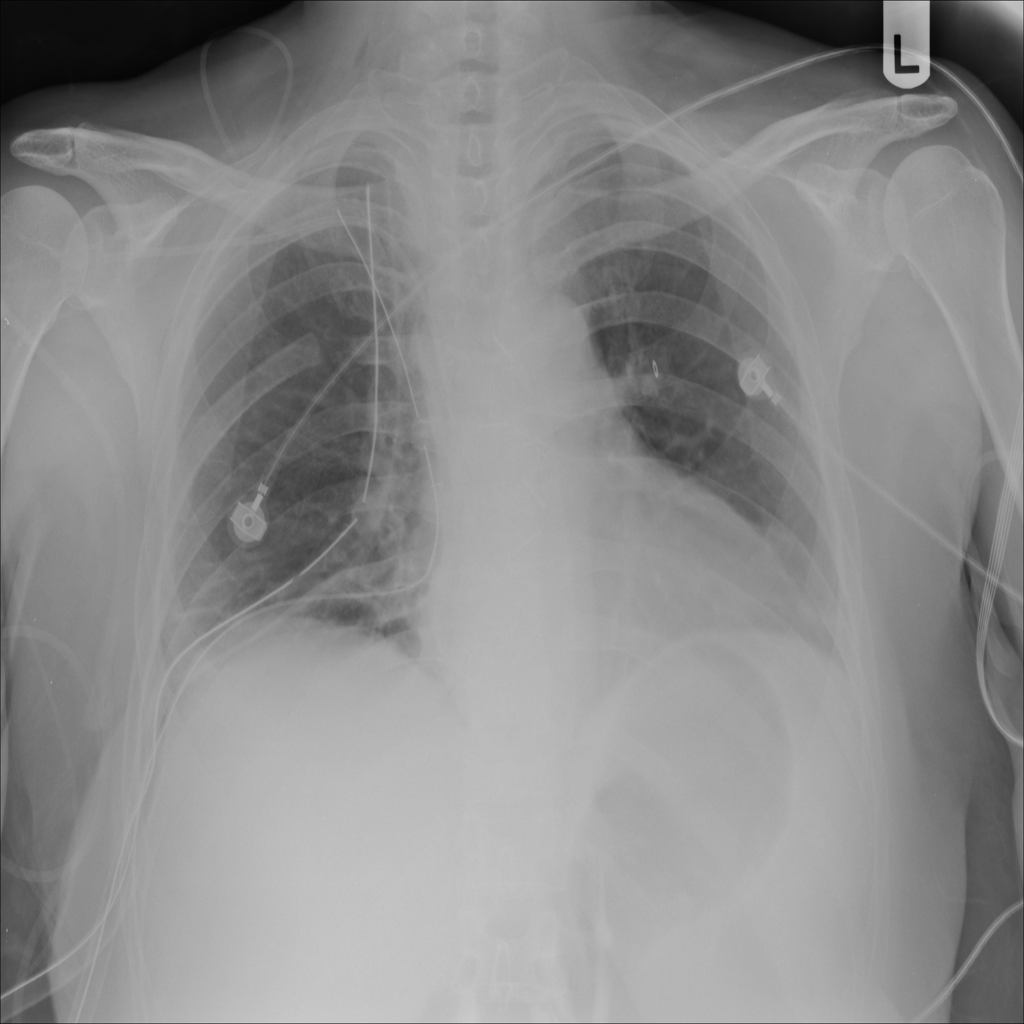

PAT-0E82 · IMG-000Emphysema

PAT-0E82 · IMG-000

AP